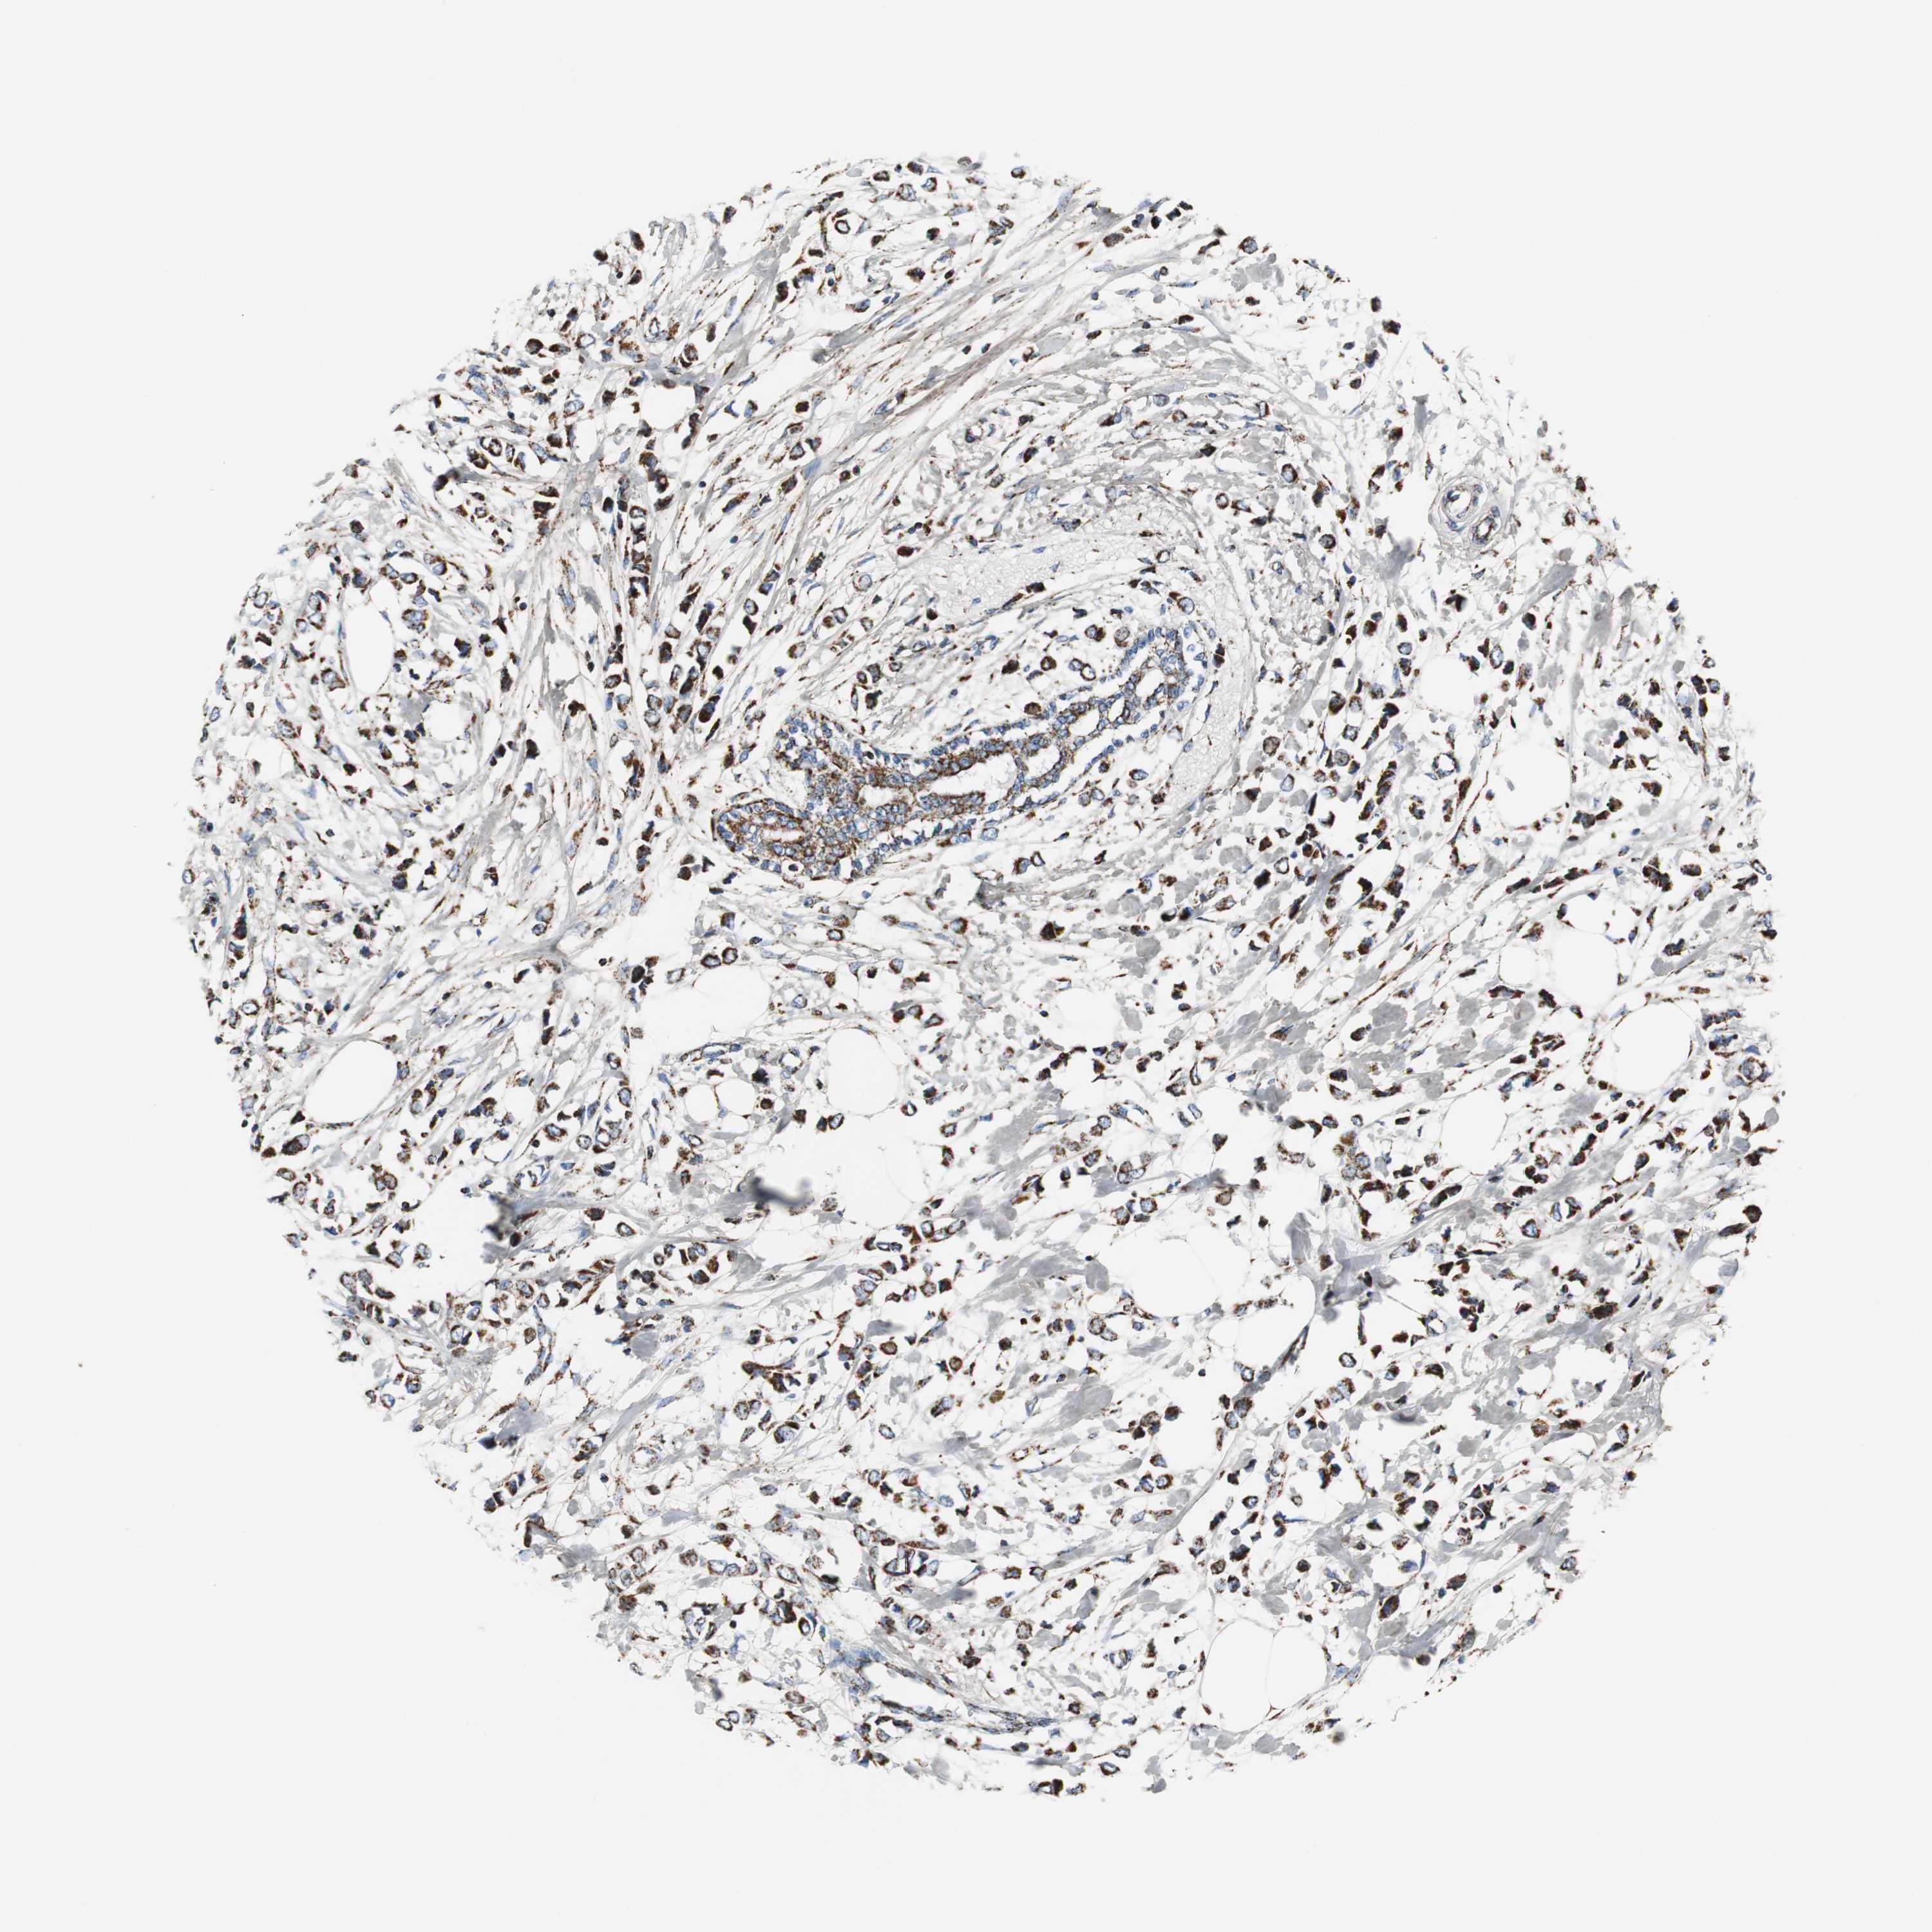

CANCER BREAST CANCER Show tissue menu

BRCA TCGA BRCA VALIDATION PROTEIN EXPRESSION